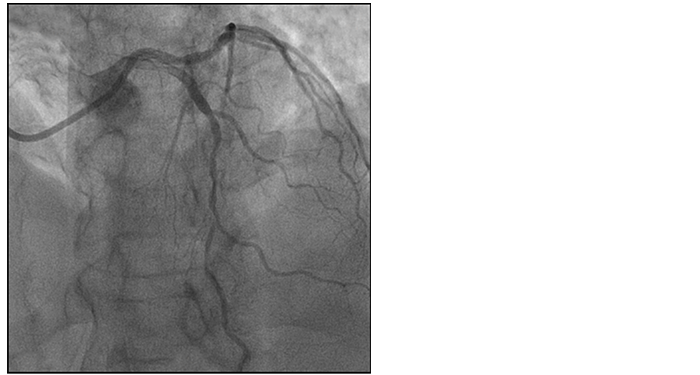

This angio shows both focal and diffuse disease.

Which areas are the most physiologically significant?

The iFR Scout pullback shows the most significant gradient in the mid-vessel lesion with diffuse proximal disease.